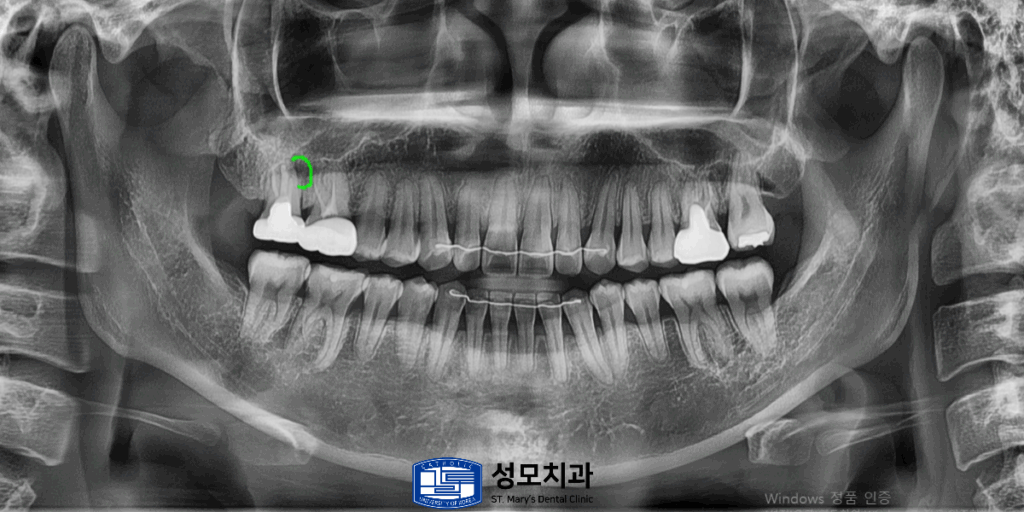

2. 치료 전 파노라마 사진

x-ray 상에서 앞쪽 뿌리 부분에

염증소견이 관찰되었습니다.

7. 치료 후 파노라마 사진

결과적으로 발치 없이 자연치를

보존할 수 있었으며 환자분 또한

미흡한 이전 처치로 인해 보존을 포기해야 하나

걱정했던 치아를 살릴 수 있어서 큰 만족을 보이셨습니다.